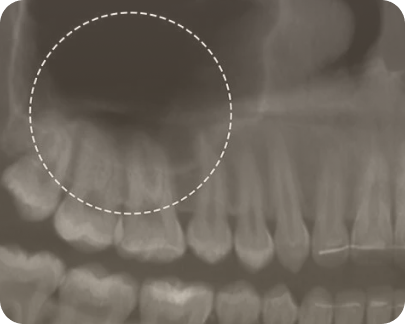

Гайморит или верхнечелюстной синусит – воспалительное заболевание придаточных пазух носа.

Зубы и гайморит